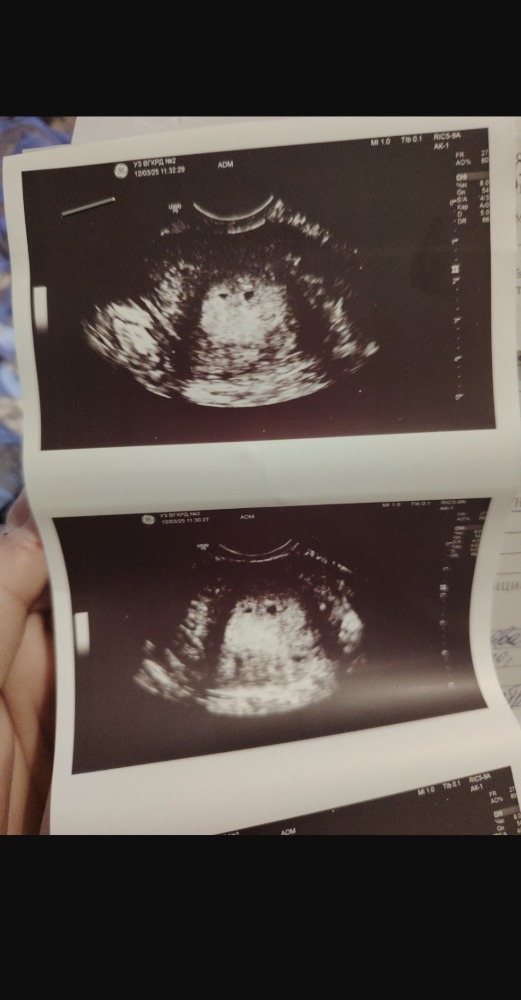

подскажите пожалуйста, была сегодня на УЗИ, врач поставил диагноз двойня под вопросом, ранний срок, 4-5 недель, но один эмбрион с желточным мешочком, а второй якобы пустой и она засомневалась эмбрион ли

Так же сказала, что второй пустой намного меньше

В роду ни с одной стороны двойни не было. Фото прилагаю

Катерина, это желточный мешочек. В плодном яйце. А желтых тех в ваших яичниках сколько? Желтое тело образуется на месте лопнувшего фолликула, соответственно, если их два - в одном яичнике или в каждом яичнике по одному, то да может быть и двойня. По снимку похоже

Марина Алташина, желточный мешочек один, а эмбриона как бы два, один пустой, не знаю может неправильно формулирую где-то, шок берет верх

Катерина, это не эмбрионы, а плодные яйца, эмбрион не может быть пустым. В плодном яйце должен появиться эмбрион и желточный мешочек. А в яичниках после овуляции образуется желтое тело, это не желточный мешочек. У вас в описании узи должны быть описаны яичники, их размер и размер желтого тела. Вот если в каждом яичнике есть желтое тело, то на фото у вас может быть два плодных яйца в которых будут эмбрионы